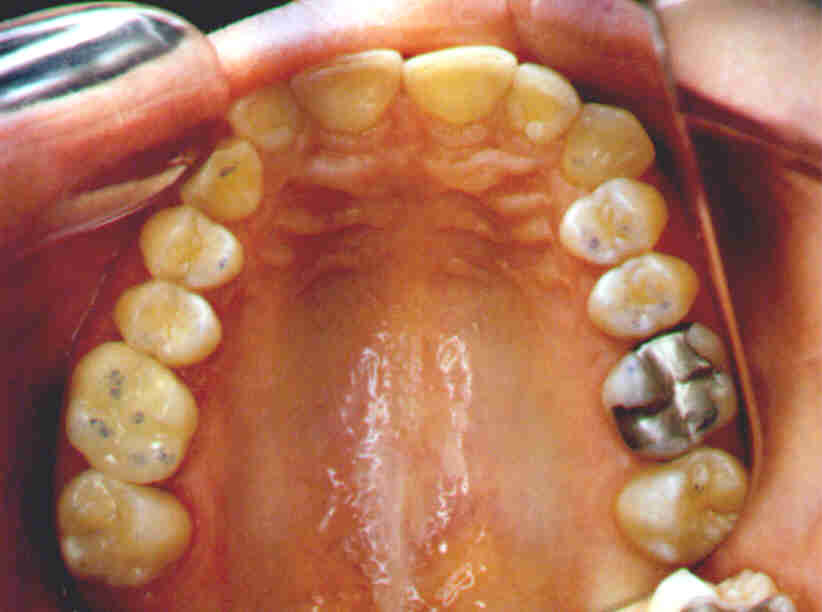

Cerec-Onlay an Zahn 16

zum Vergleich Amalgamfüllung an Zahn 26

Einwandfreie Funktion wie die Zentrik-Kontakte zeigen